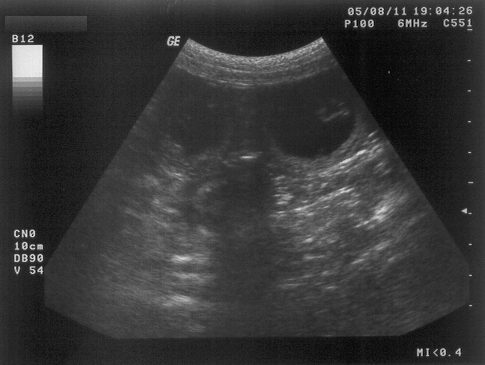

11.08.2005

So ... nun steht es definitiv fest (als ob ich es nicht schon die ganze Zeit gewusst hätte).

Ich bin schwanger und meine Welpen sollen im September (ca. 15.09.2005) zur Welt kommen.

Ein "bewegtes" Ultraschallbild findet ihr übrigens hier (Ladezeiten beachten und abwarten)

Anklicken (Ladezeiten beachten und abwarten)